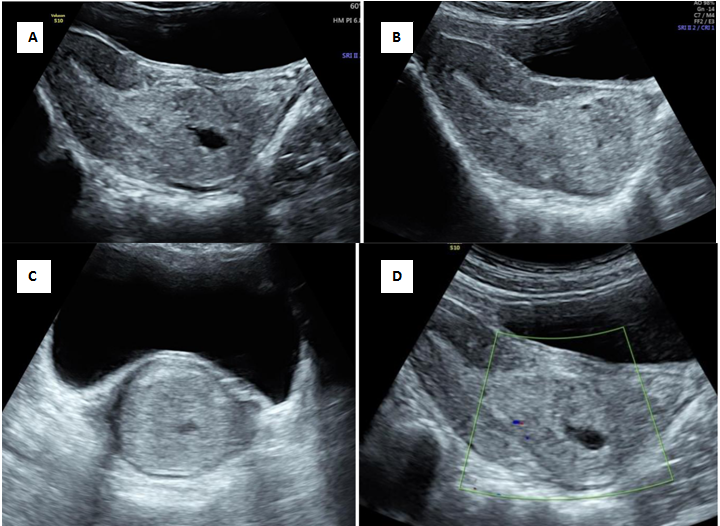

An abortion in progress or the inevitable abortion is the condition where the products of conception have detached from the implantation site and continuation of pregnancy is not possible. The ballooning of the cervical canal due to retention of the abortus by the resistant external os in spontaneous abortion can rise the suspicion of cervical pregnancy.1 A non-viable sac passing through the cervix will have no peritrophoblastic flow and this serves as an initial clue. Figure 1 is an illustration of cervical stage of miscarriage, showing an open external os with products of conception in the cervical canal with absent peritrophoblastic flow. Short-term follow-up of a failed pregnancy will demonstrate lack of interval growth, and confirm that the gestational sac is not fixed in location and will have a positive sliding sign.2 Both cervical ectopic pregnancy and CSP often contain live embryos with detectable cardiac activity, while an abortion in progress will not. A combination of gray scale and colour doppler findings helps to differentiate the two entities.3,4

Figure 1 Cervical stage of miscarriage.

A) Transabdominal ultrasound showing echogenic mass seen in the cervical canal with splaying of anterior and posterior lip of cervix[*] B) Demonstration of open external os with products of conception in cervical canal C) Transverse section of cervix showing distended cervix with echogenic mass D) No evidence of peritrophoblastic vascularity seen surrounding mass.